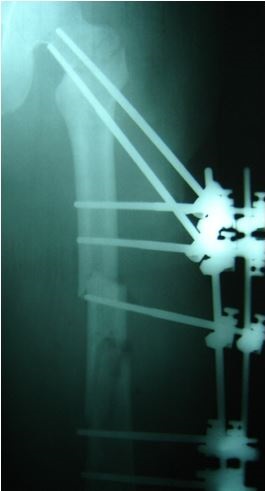

Radiografía de aplicación de ATLAS en paciente politraumatizado

La patente concedida en Estados Unidos se denomina "Atlas" y consiste en un sistema de fijación externa para tratar fracturas de huesos, que agiliza los tiempos de sanación y reduce los costos de tratamientos ortopédicos, debido al sistema para fijar los huesos afectados en la posición adecuada.

El sistema de fijación permite activar todos los grados de libertad entre los elementos que conectan y es hecho con acero inoxidable y fibra de carbono lo que permite, al médico ortopedista, adaptar el tratamiento en menos tiempo y con más comodidad para el paciente, así sean posiciones complicadas.

Aunque el dispositivo está diseñado y validado para ser empleado esencialmente en pacientes con fracturas por trauma, podría utilizarse en tratamientos veterinarios, pues cuenta con pruebas biomecánicas de laboratorio y con pruebas clínicas, con resultados satisfactorios.